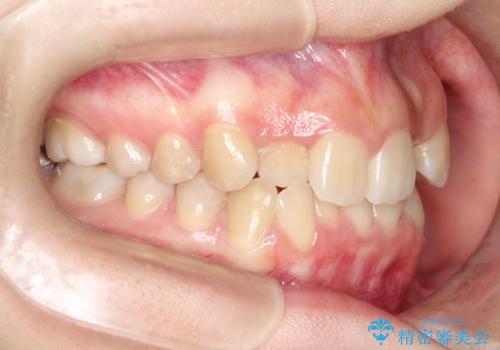

- 前歯のデコボコ(叢生)と、前歯が上下逆の咬み合わせ(反対咬合)を主訴にご来院されました。精密検査の結果、歯列全体のスペースが不足していることが判明。患者様のご希望に合わせ、透明で目立ちにくい**インビザライン(マウスピース矯正)**による治療計画を立案しました。歯を抜かずに、歯列全体を奥(遠心)へ移動させることで、歯が並ぶスペースを確保し、叢生と反対咬合を同時に改善することを目指します。

今回の矯正治療では、透明なマウスピース型の装置インビザラインを使用しました。この装置は目立たず、取り外しが可能なため、食事や歯磨きも普段通り行えます。治療は、緻密な治療計画に基づき、段階的に作製されたマウスピースを交換していくことで、遠心移動という方法で奥歯から徐々に歯列全体を後方へ動かしました。これにより、不足していたスペースを確保し、前歯のデコボコを解消。同時に、上下の歯の前後的な関係を改善することで、反対咬合も正常な咬み合わせへと導きました。見た目も機能も改善し、自然で美しい笑顔を獲得していただけました。